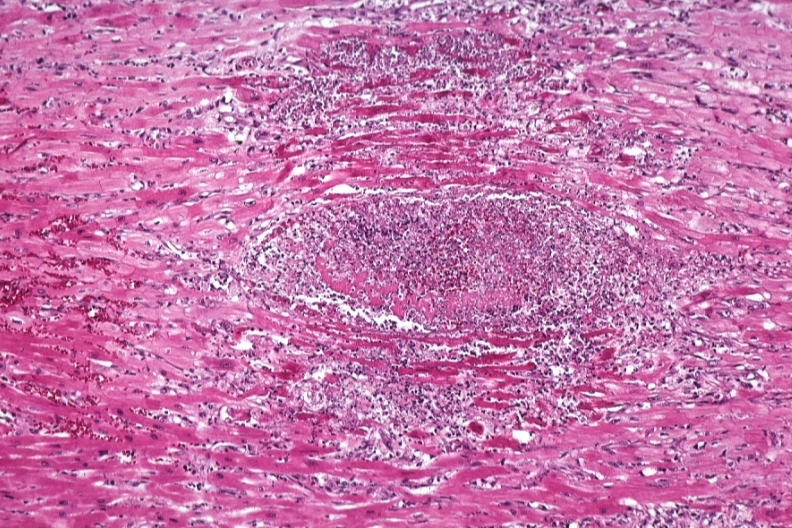

HISTOLOGY: CARDIOVASCULAR: HEART: Abscess: Micro H&E high mag abscess due to Candida with marked muscle necrosis leukemia case